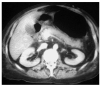

La paciente acudió al Servicio de Urgencias por vómitos y malestar general, que se atribuyeron a la medicación anti-VIH por lo que se decidió suspenderla. La analítica realizada no mostró alteración alguna, por lo que fue dada de alta al domicilio. En esa oportunidad no se le realizó gasometría. Cuarenta y ocho horas más tarde ingresó en la unidad de cuidados intensivos (UCI) por bajo nivel de conciencia (escala de coma de Glasgow [GCS], 7 puntos), hipotensión (90/60 mmHg) e importante aumento del trabajo respiratorio por lo que se la intuba y conecta a la ventilación mecánica (FiO2 40% y presión positiva a final de la espiración [PEEP] 0). En la exploración destacaban una hepatomegalia y edemas. En la analítica de sangre se encontraron los siguientes hallazgos: pH, 6,77; PaCO2, 21 mmHg; PaO2, 62 mmHg; HCO3, 4 mEq/l; exceso de bases, 31,6 mEq/l; hemoglobina, 13 g/dl; leucocitos, 25.400/ml (83% neutrófilos); plaquetas, 169.000/ml; urea, 50 mg/dl; creatinina, 2,7 mg/dl; Na+, 155 mEq/l; K+, 2,2 mEq/l; glucosa, 33 mg/dl; bilirrubina, 0,8 mg/dl; GOT, 68 U/l; GPT, 30 U/l; tasa de protrombina, 44%; fibrinógeno, 144 mg/dl; CK, 397 U/l; CK-MB, 123 U/l; troponina I, 0,15 ng/ml; etanol, 5 mg/dl; amilasa, 1.493 U/l; ácido láctico, 145,6 mmol/l (rango normal 4,5-19,8); CD4+, 95; carga viral, 199 copias/ml. La radiografía de tórax mostraba atelectasias segmentarias bibasales (fig. 1). En la tomografía computarizada de abdomen se apreciaba hepatomegalia hipodensa, esteatosis y mínima cantidad de líquido libre en ambas gotieras y en la pelvis; el páncreas, los riñones, el bazo y las suprarrenales eran normales (fig. 2).

Figura 2. Tomografía computarizada abdominal. Hepatomegalia hipointensa con esteatosis. Importante distensión gástrica. Mínima cantidad de líquido libre en ambas gotieras y en la pelvis. El páncreas, los riñones, el bazo y las glándulas suprarrenales no muestran alteraciones.